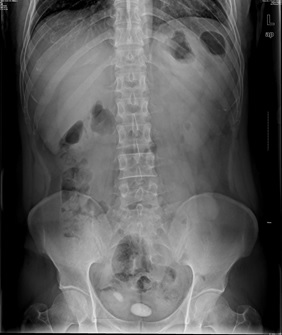

05卷-4.男,55岁,反复尿频、尿痛、排尿困难半年

本题答案:B

【该题针对“ X线-泌尿系结石 ”知识点进行考核】